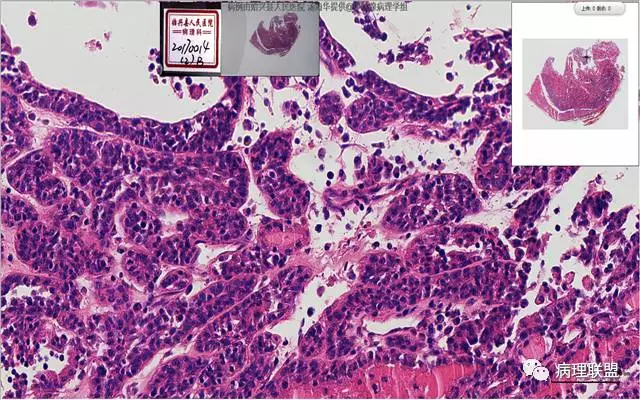

患者,女,45岁,发现双侧甲状腺肿物半月余。大体所见:左侧甲状腺肿物:4.3*5*4cm肿物一个,包膜完整,光滑,质脆,中央见出血。右侧甲状腺组织:3*1.6*1.5cm及1*1*0.8cm组织两块,其中较大的组织切开见内有0.8cm及1.2cm两个,质硬,灰白色,界不清,较小的,切开见灰黄色,质脆。